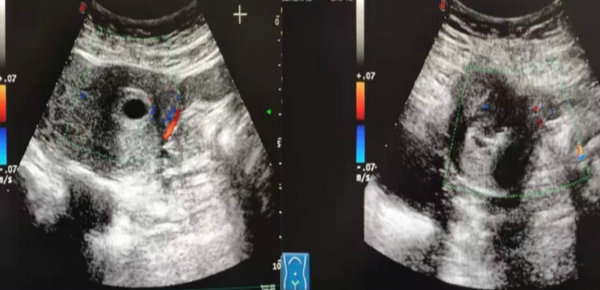

入院当天下午,刘慧临主任便为患者行超声介入下聚桂醇硬化,第二天血HCG明显下降,第三天高主任顺利施行清宫术,操作过程仅5分钟,手术过程十分顺利,术中患者仅少量出血。

彩色多普勒提示孕囊周边血流丰富

聚桂醇硬化前后对比

超声介入下聚桂醇注射联合清宫术治疗剖宫产瘢痕妊娠疗效显著,在注射后可直接损伤血管内皮,促进血栓形成,粘附于注射部位血管内,继而产生无菌性炎性病变和组织纤维化。而且注射剂增大了血管内皮的接触面,延长接触时间,可以达到快速硬化的效果。最终,纤维化条索代替病理性血管,导致病理性血管永久性闭塞,达到快速、有效硬化的目的。超声引导下聚桂醇剖宫产瘢痕妊娠多点局部注射后,使孕囊局部的浅表小面积血管产生一定的影响,能促进其快速硬化。病灶局部血液循环受阻,继而获得理想的压迫止血效果,减少后续清宫过程中的阴道出血量,获得更好的治疗效果,促进患者的术后恢复。